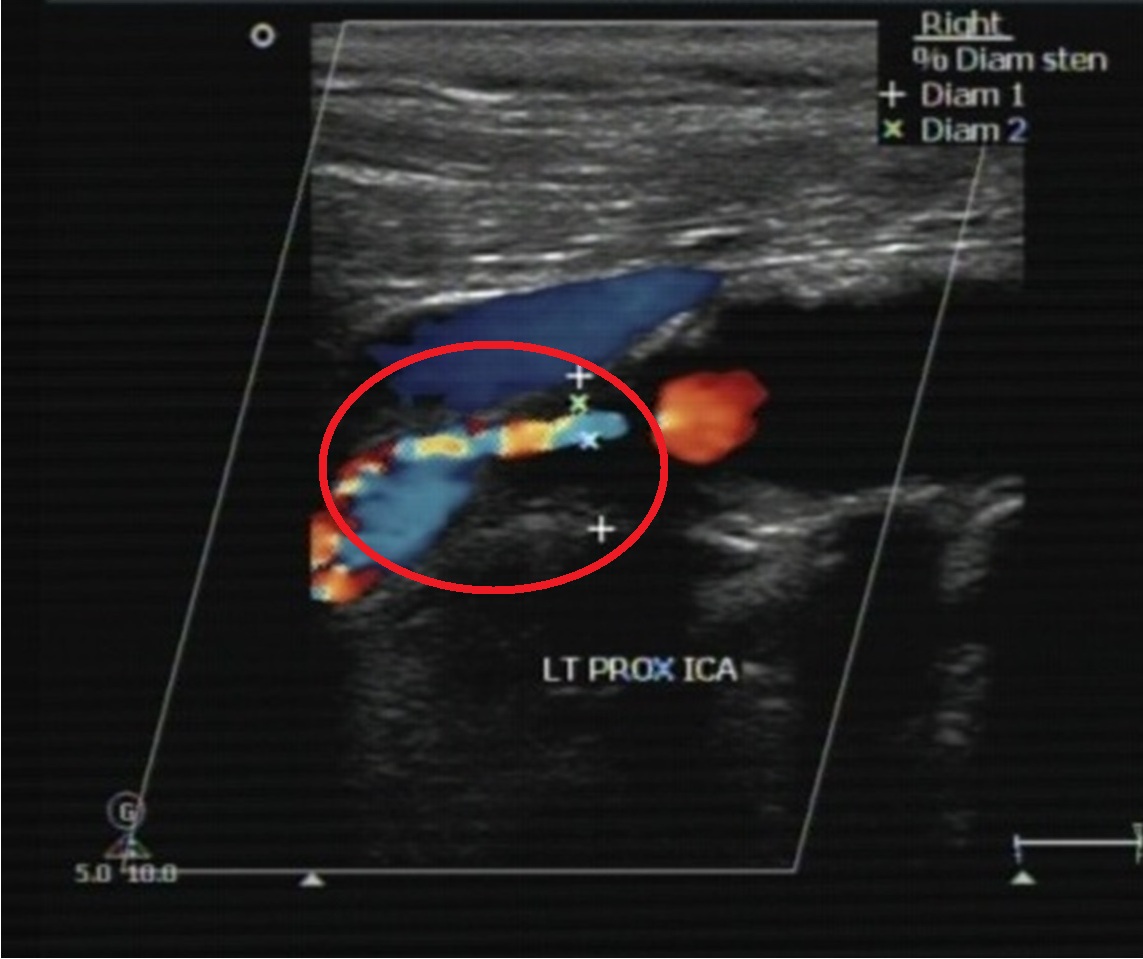

透過頸動脈超音波掃描,可協助病人及早發現頸動脈阻塞問題(紅圈處)。

在頸動脈完全阻塞之前,常出現下列症狀:不明原因的昏厥、手腳無力發麻(尤其是半側的症狀)、暈眩、大舌頭等。當頸動脈阻塞較嚴重時,會引起半側大腦嚴重梗塞,還可能造成半側癱瘓、臥床等後遺症,甚至危及性命。如能在頸動脈尚未完全栓塞前,利用頸動脈超音波、電腦斷層、核磁共振、血管攝影等方法檢測出,在符合條件下,可進行頸動脈支架置放術,把狹窄的頸動脈撐開,增加腦部灌流,就可解決潛在的中風危機。